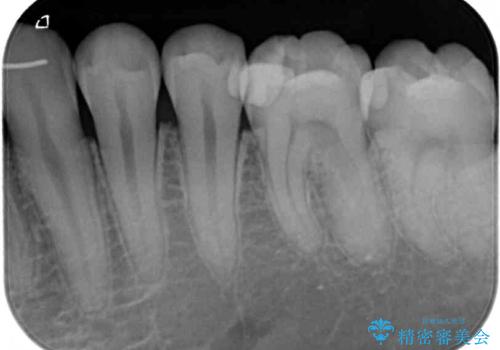

目視やレントゲン写真からは、以前処置された部分に大きな問題は認められませんでしたが、冷たい風をかけると強い痛みを感じる状態でした。

患者様と相談の上、詰め物を全て外した上でむし歯があるかどうかを確認し、セラミックインレーで精密な修復治療を行うこととしました。